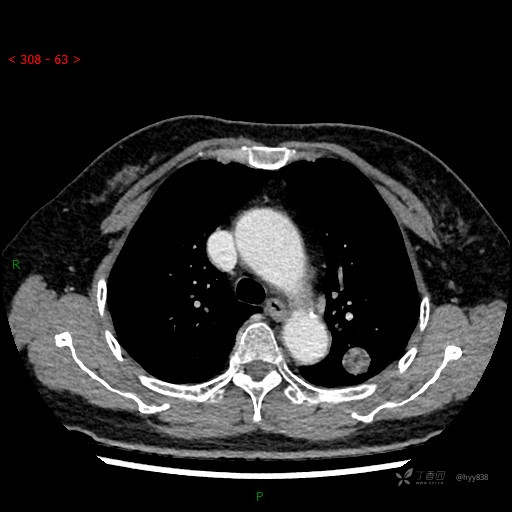

静脉期

各期CT值:28hu、58hu、69hu